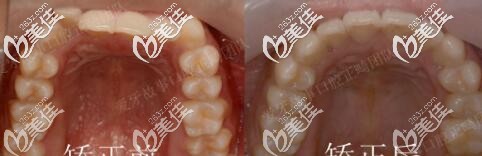

图五下前牙对比

矫正用了1年半,地包天明显改善,牙弓也扩开了。正畸期间口腔护理很重要,如果出现了口腔有异味或炎症,就要隔两到三天使用牙套清洁片把牙套泡一泡,必要时可用酒精棉片对牙套进行消毒。